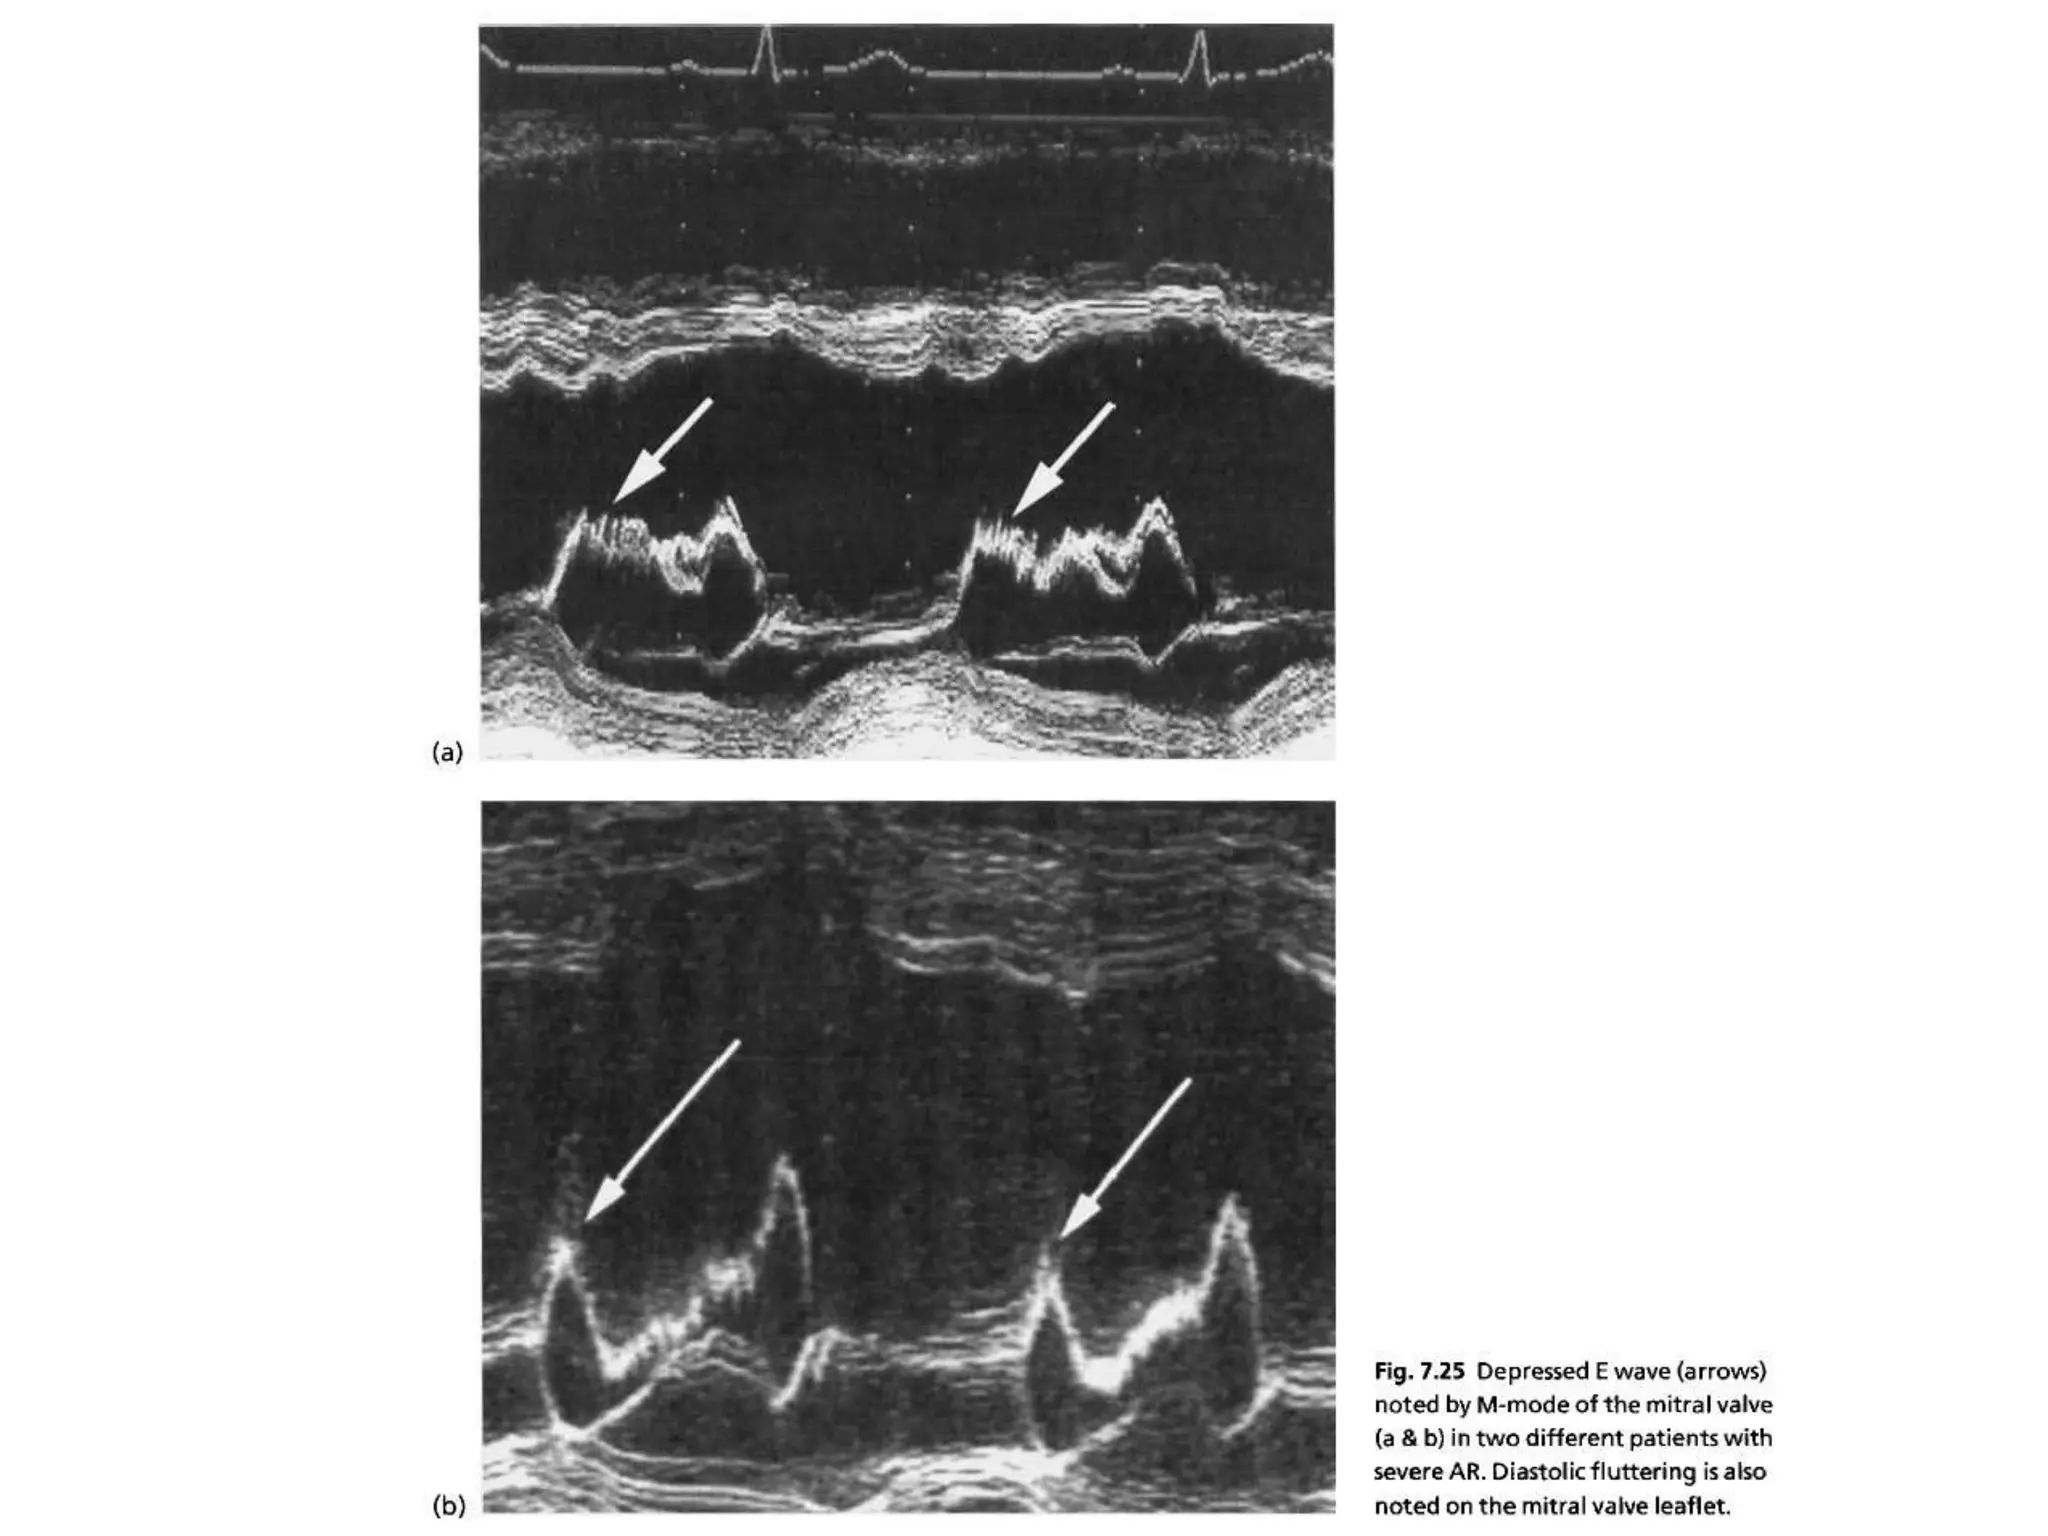

ACUTE VS CHRONIC • Shape of the envelope CW doppler • Rate of deceleration of flow • Premature mitral valve closure • Endocarditis,dissection • Normal lv dimensions

• Regurgitant dopplersignal is a function of pressure gradient between aorta and LV • Mild AR –small increase in LVEDP-gradual decline and flat deceleration slope • Severe AR –LVEDP rises rapidly-rapid decline